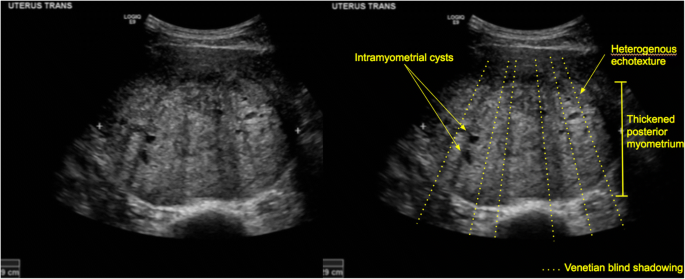

Hypertrophy of uterus N852 is a billable/specific ICD10CM code that can be used to indicate a diagnosis for reimbursement purposes The 21 edition of ICD10CM N852 became effective on This is the American ICD10CM version of N852 other international versions of ICD10 N852 may differ In addition to an enlarged uterus, symptoms of uterine fibroids may include Feeling of fullness or pressure in the lower abdomen Heavy, painful, and/or longlasting periods, sometimes with the passage of blood clots Bleeding between periods Constipation Frequent urination Pain during intercourseDiffuse uterine process and the effect of fibroids—The reviewers scored 22 of the 73 sonograms as showing a diffuse uterine process when the uterus was enlarged and heterogeneous in echotexture (Table 2 and Fig 1A, 1B) Discrepant interpretations

Venetian Blind Shadowing On Ultrasound Springerlink

Coexistence Of A Fibroid And Adenomyosis In A 54 Year Old Woman Download Scientific Diagram